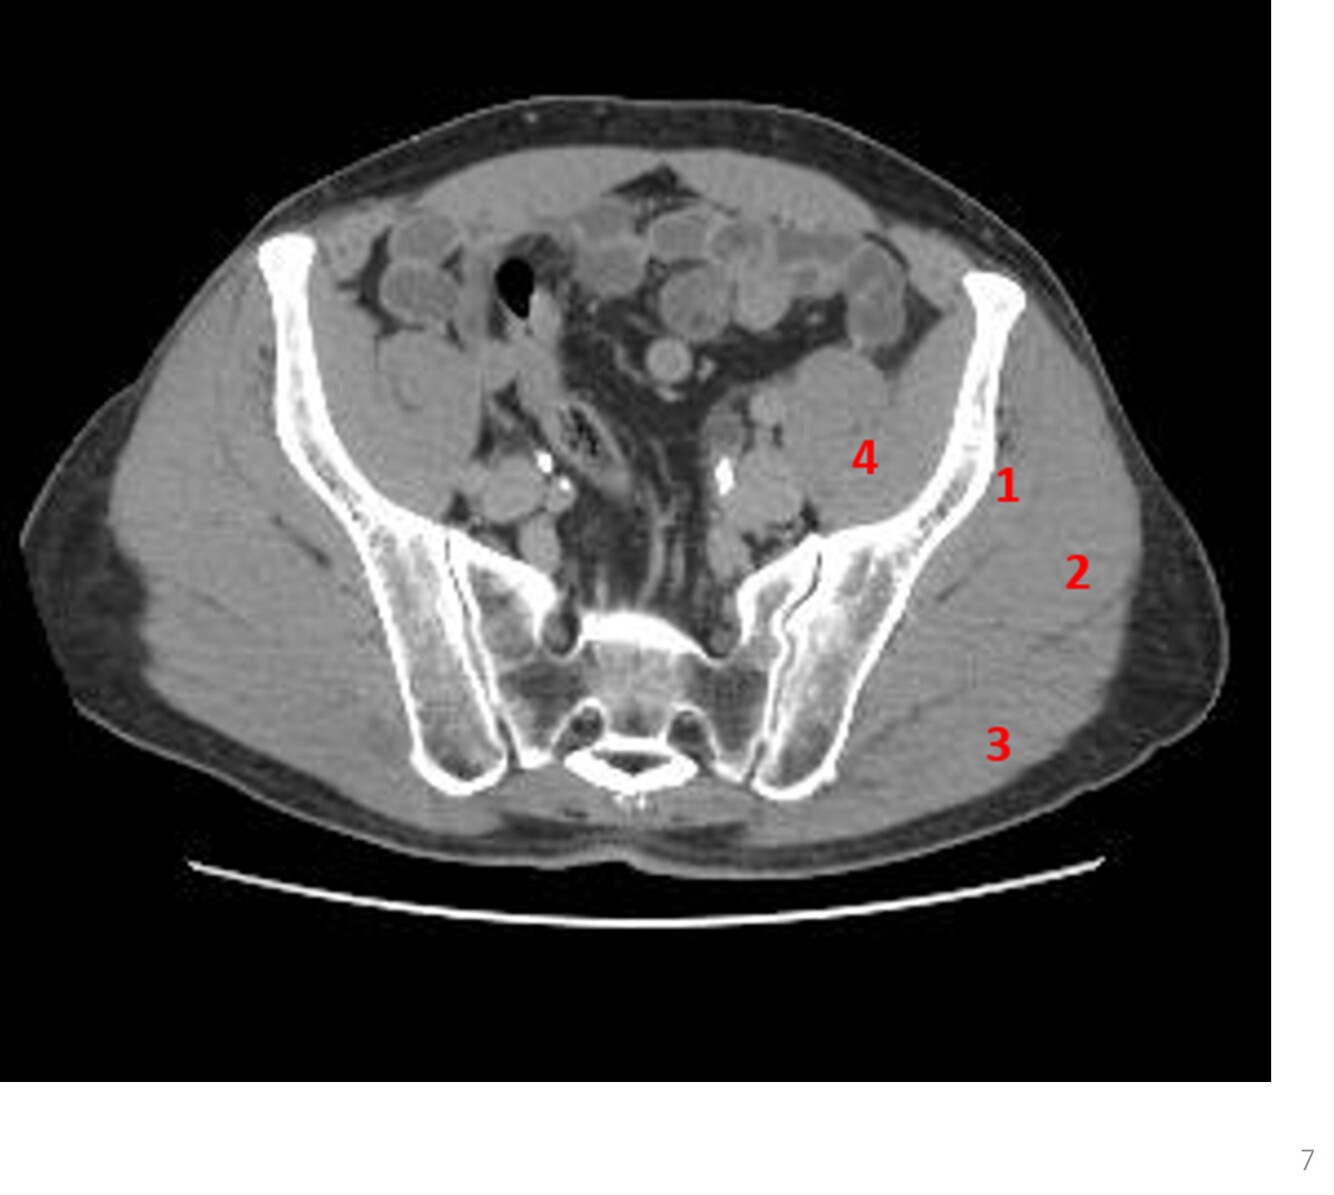

Q

Label 1-5

A

1. Rt femoral head

2. Rt ischium

3. Rt superior pubic ramus

4. Lt greater trochanter

5. Lt gluteus maximus